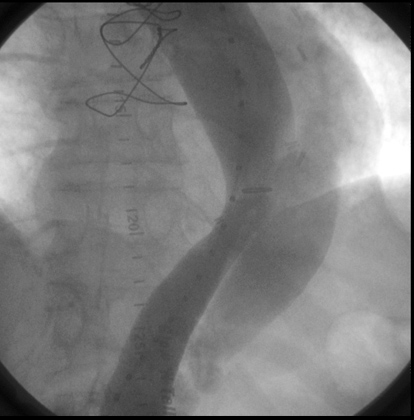

Radiologic Criteria for Dissection in Aortography:

• Aortography has long been considered the study of choice for evaluating suspected aortic dissection.

• It is performed by injecting the contrast agent retrograde through the femoral artery.

• The diagnosis of aortic dissection can be made on the basis of direct or indirect angiographic signs.

• The direct signs (which are diagnostic) include visualization of a double lumen or an intimal flap.

• The indirect signs (which are suggestive), include compression of the true aortic lumen by the false lumen, thickening of the aortic wall, or aortic insufficiency.

• Aortography is advantageous in that it can detect several complications including aortic insufficiency, involvement of the branch vessels, thrombus in the false lumen, and in some cases, involvement of the proximal coronary arteries.

• Aortography has a reported sensitivity of 88% and a specificity of 94%.

• In addition to its limited sensitivity, there are other disadvantages to aortography such as the risks involved with any invasive procedure requiring contrast.

• There is a high cost associated with aortography.

Dissecting aneurysm Angiogram